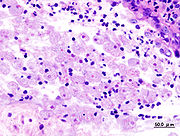

ويتم التشخيص المجهري بمشاهدة الأتاريف أو الكيسات في نماذج طازجة من البراز أو محفوظة بطريقة مناسبة، أو في لطاخات رشافات أو كشاطات جمعت من خلال التنظير المستقيمي أو رشافات الخراجات أو النسج المصابة. وإن وجود الأتاريف المحتوية على كريات الدم الحمراء دليل على داء الأميبات الغازي. ويجب أن يقوم بفحص النماذج الطازجة فاحص مجهري مدرب، إذ يجب التفريق بين هذا الطفيلي والأميبات اللا ممرضة والبلاعم macrophages. إن فحص 3 عينات على الأقل سيزيد من حصيلة الكائنات الطفيلية من 50% في عينة واحدة إلى 85-90%. ولقد توفرت مؤخراً اختبارات للكشف عن المستضدات النوعية في البراز، إلاَّ أنها لا تفرق بين العوامل الممرضة من غير الممرضة. كما تتوافر أيضاً مقايسات نوعية للمتحولة الحالة للنسج مثل EIA or PCR (يجرى EIA or PCR على براز طازج غير محفوظ). وقد تدعو الحاجة أحياناً إلى الاستعانة بخدمات المختبرات المرجعية. وإن كثيراً من الاختبارات السيرولوجية متاحة كمساعدات إضافية في تشخيص داء الأميبات خارج المعوي ـ كالخراجة الكبدية ـ عندما يكون فحص البراز سلبياً في الغالب. وتفيد الاختبارات السيرولوجية كثيراً لا سيما الانتشار المناعي ومقايسة الممتز المناعي المرتبط بالإنزيم (ELISA) في تشخيص المرض الغازي. أما التصوير الومضاني والتصوير بالصدى (ما فوق الصوت) والتصوير المقطعي المحوري المُـحَوْسَب CAT فتفيد في إظهار الخراج الكبدي وتحديد موقعه، ويثبت التشخيص عندما تترافق الحالة باستجابة نوعية ضدية للمتحولة الحالة للنسج.